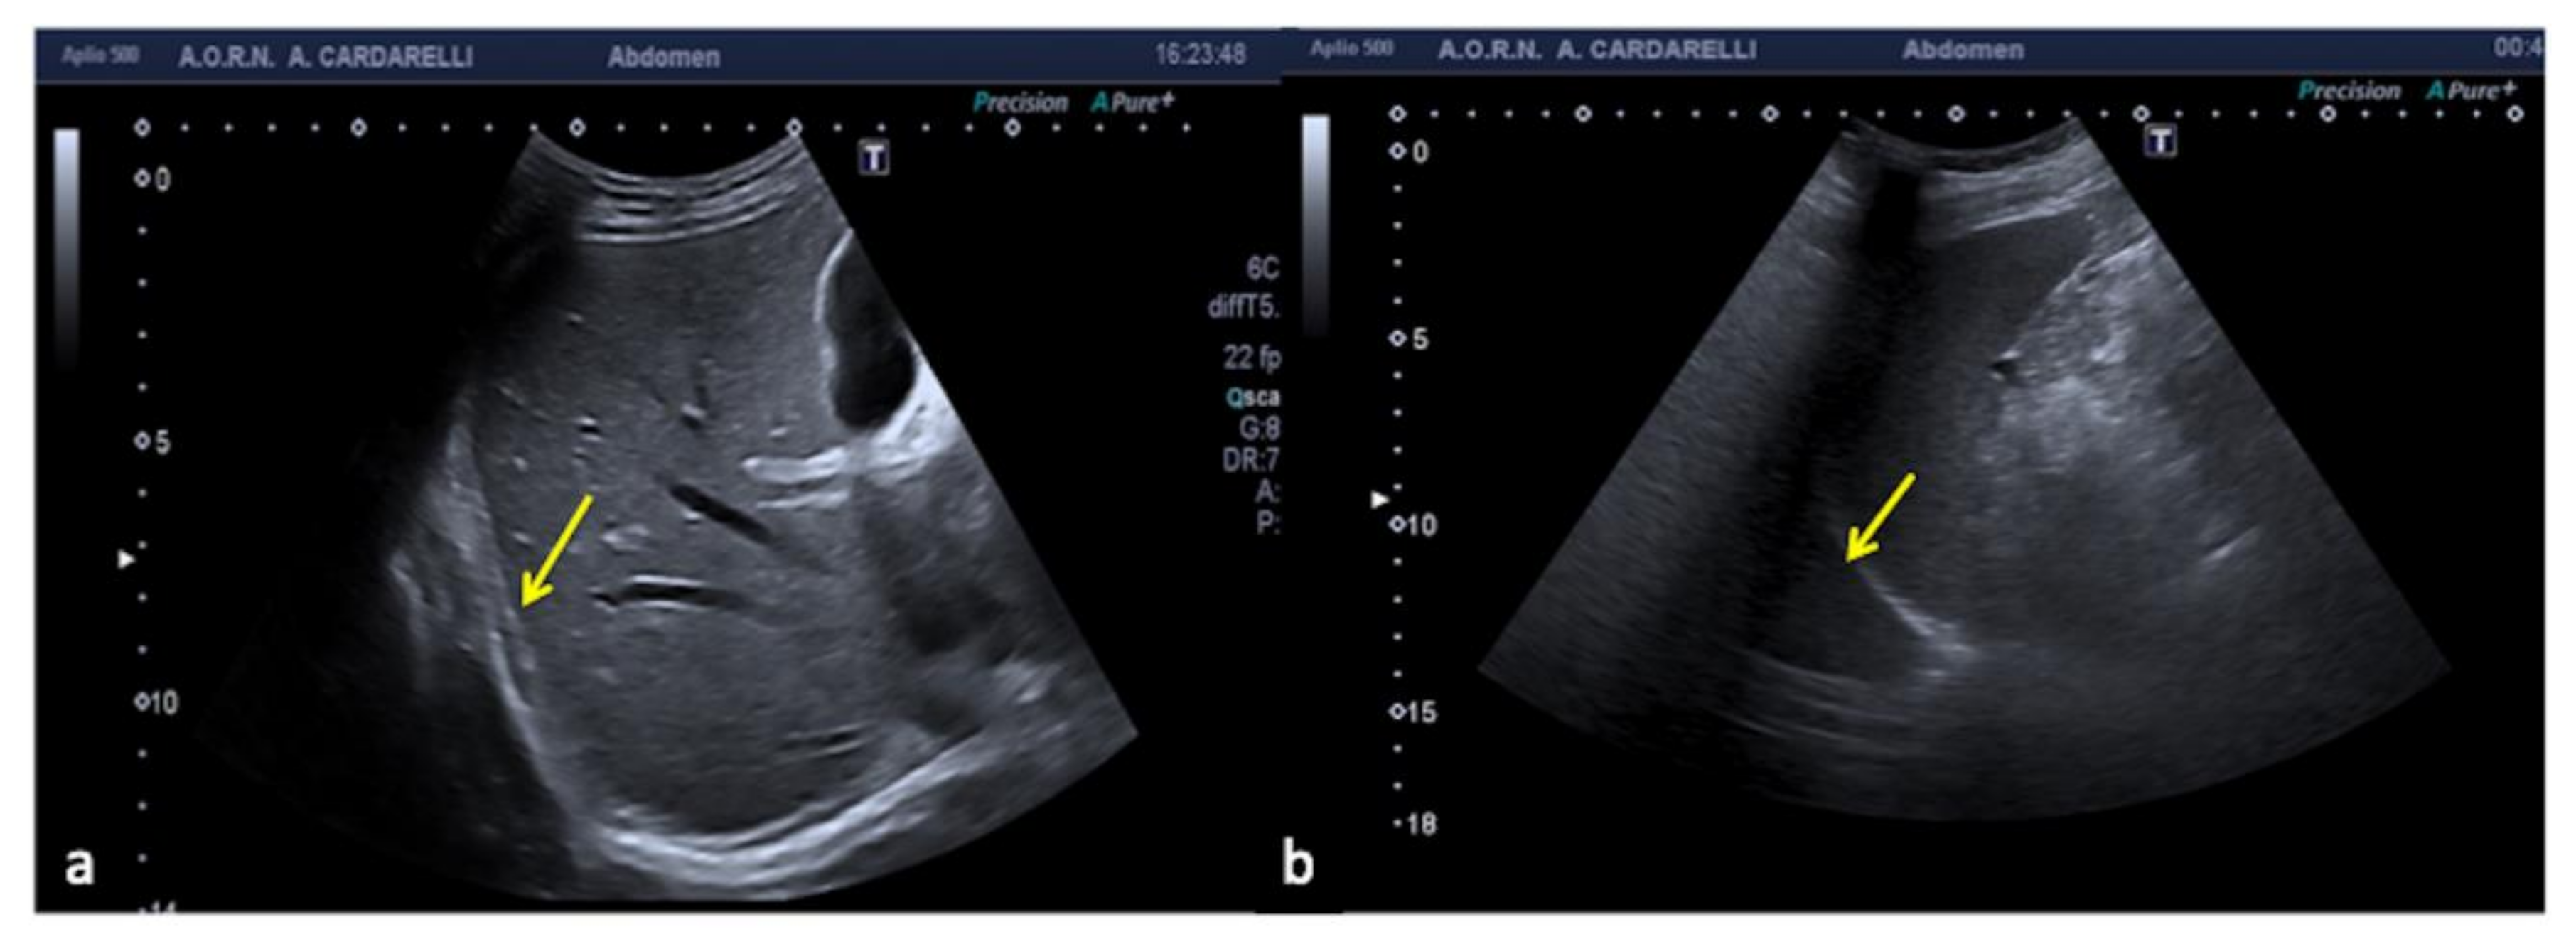

3.1.7. Anisotropy